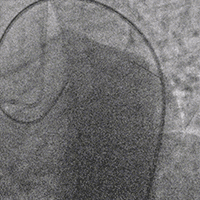

直接使用G3导丝rendezvous,球囊扩张后行IVUS检查确定血管直径及支架落脚点。

D1释放DCB,LAD植入支架后D1血流影响,工作导丝找回后使用球囊扩张并kissing。

造影发现LAD远端病变仍较重,释放DCB。

复查造影并行ivus检查 支架贴壁良好 无累及夹层。

RCA中段扩张后出现夹层,植入DES。